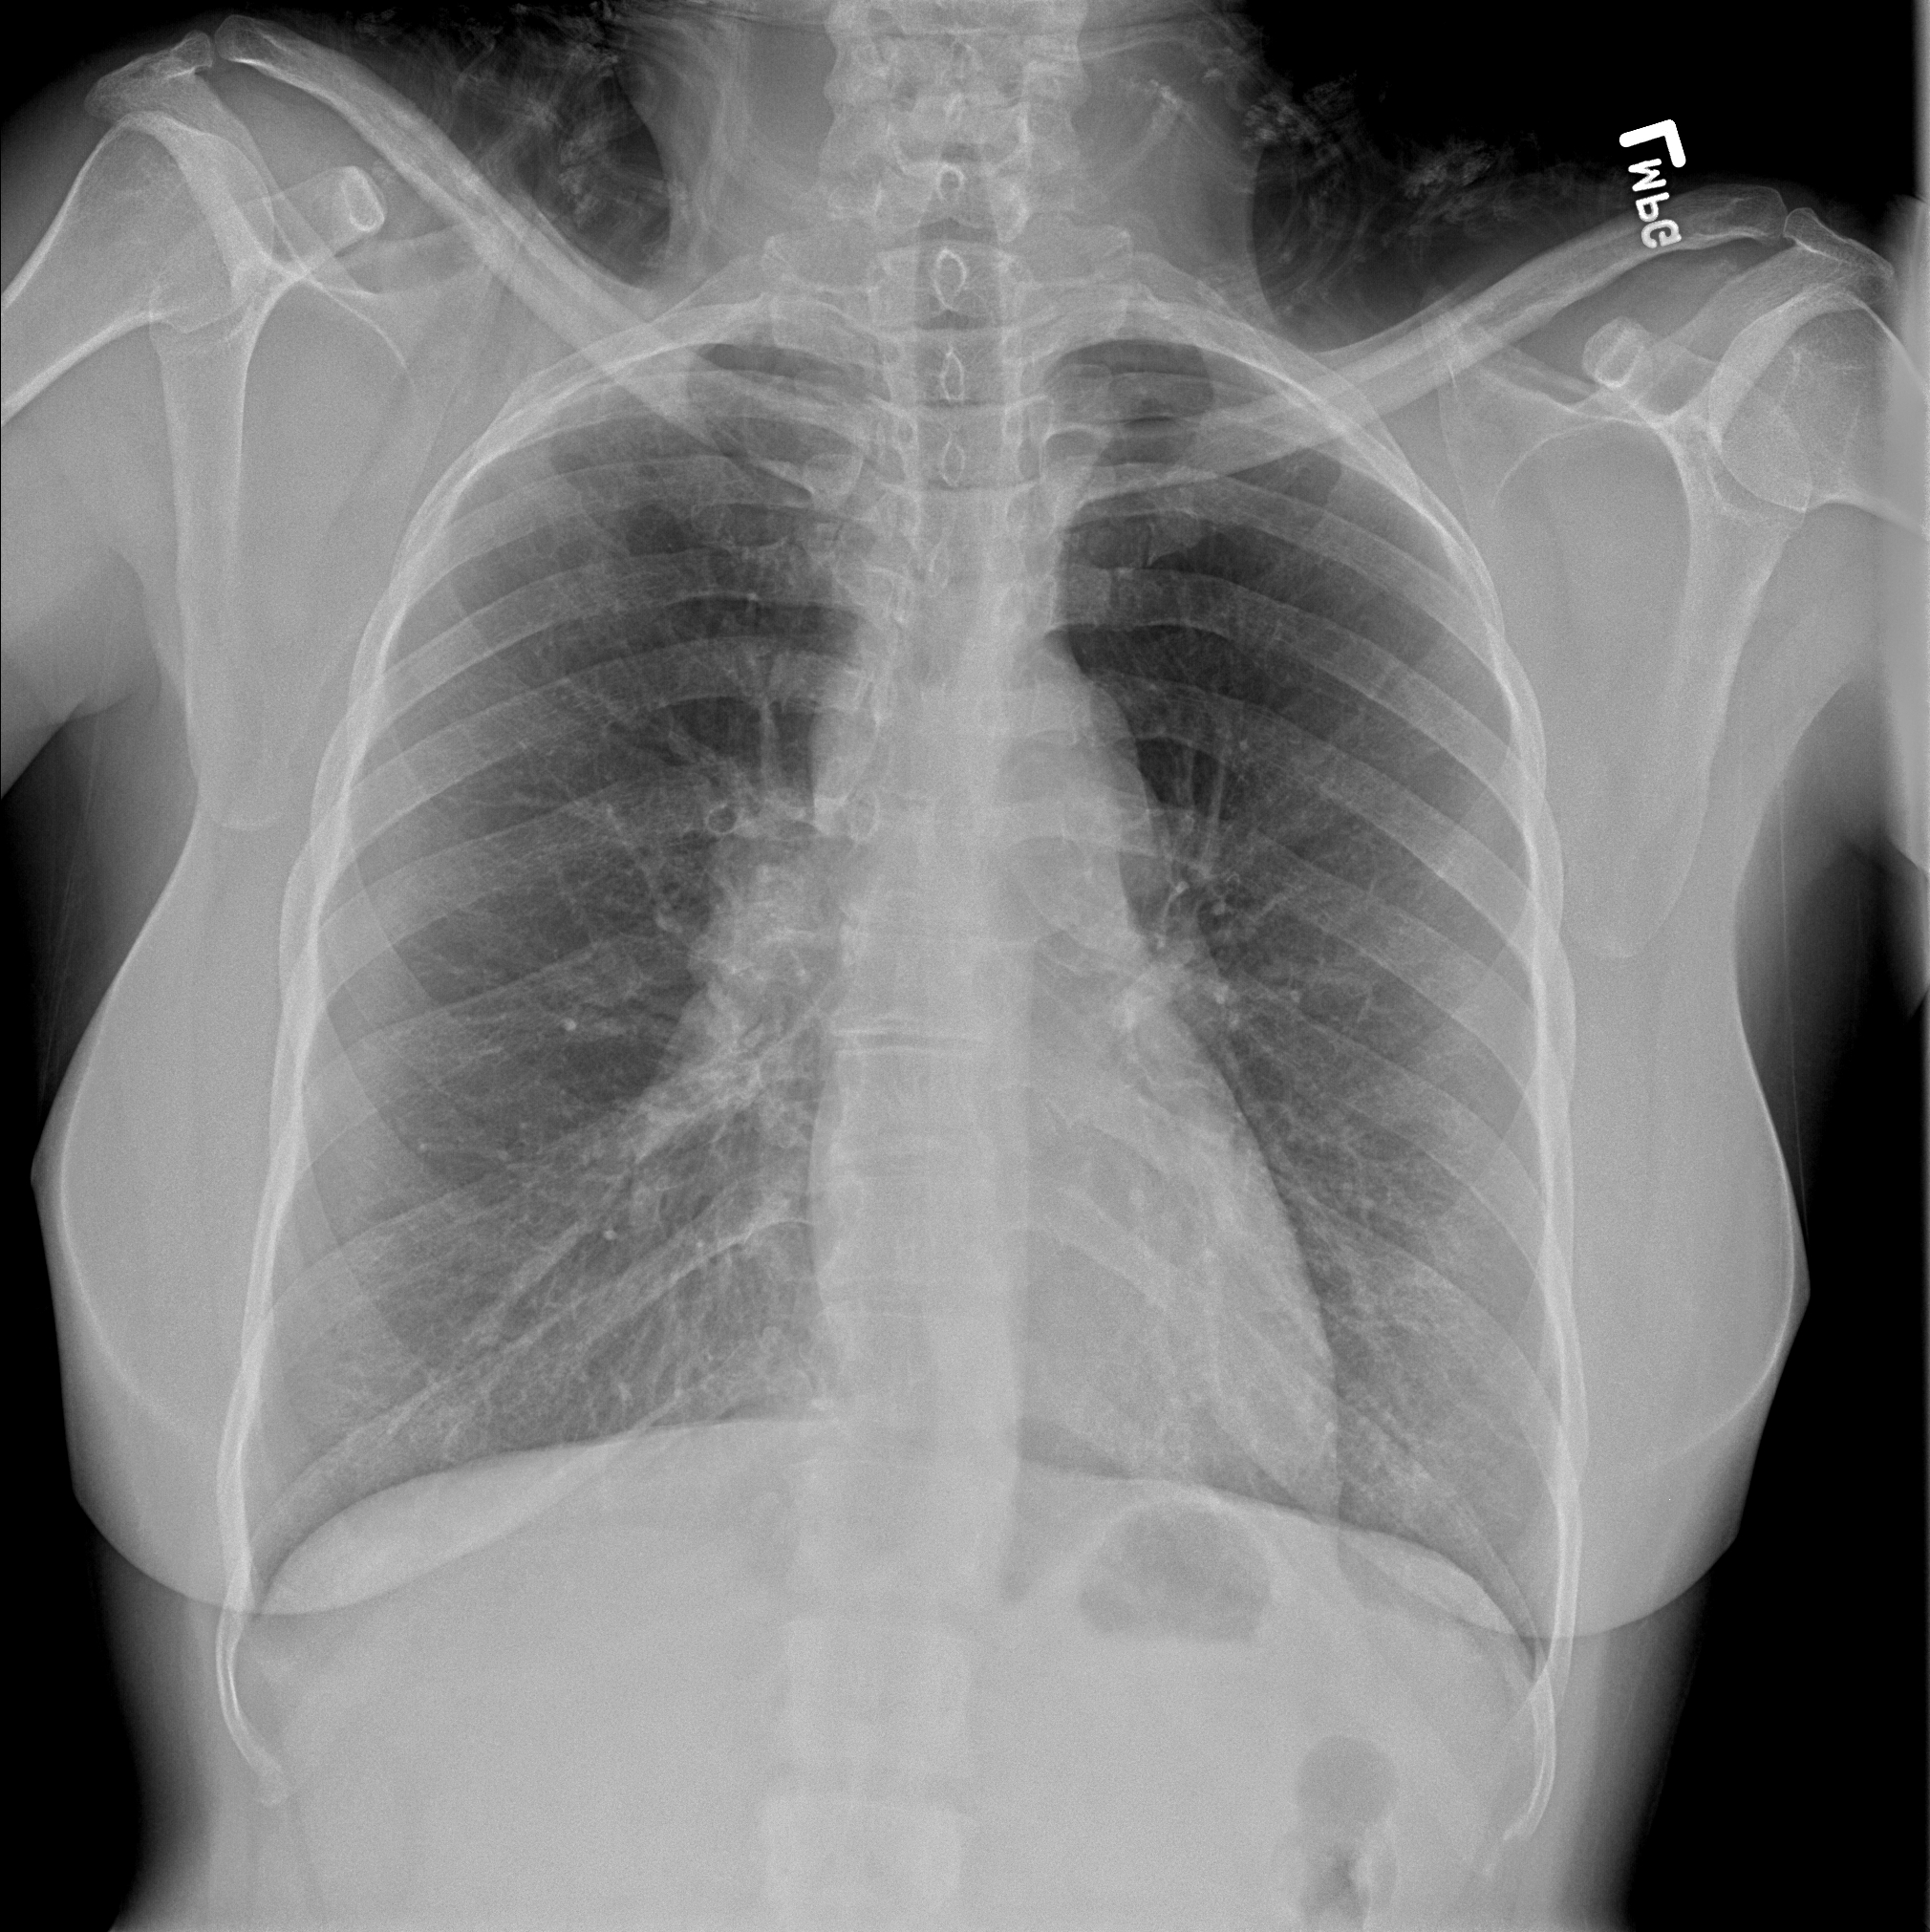

Practice Cases